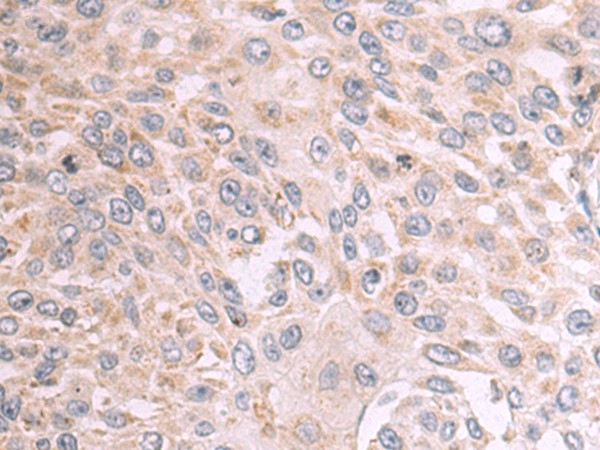

分类: 科研抗体货号: P10713别名: B7X; B7H4; B7S1; B7-H4; B7h.5; VCTN1; PRO1291; RP11-229A19.4应用: IHC反应种属: Human, Mouse, Rat